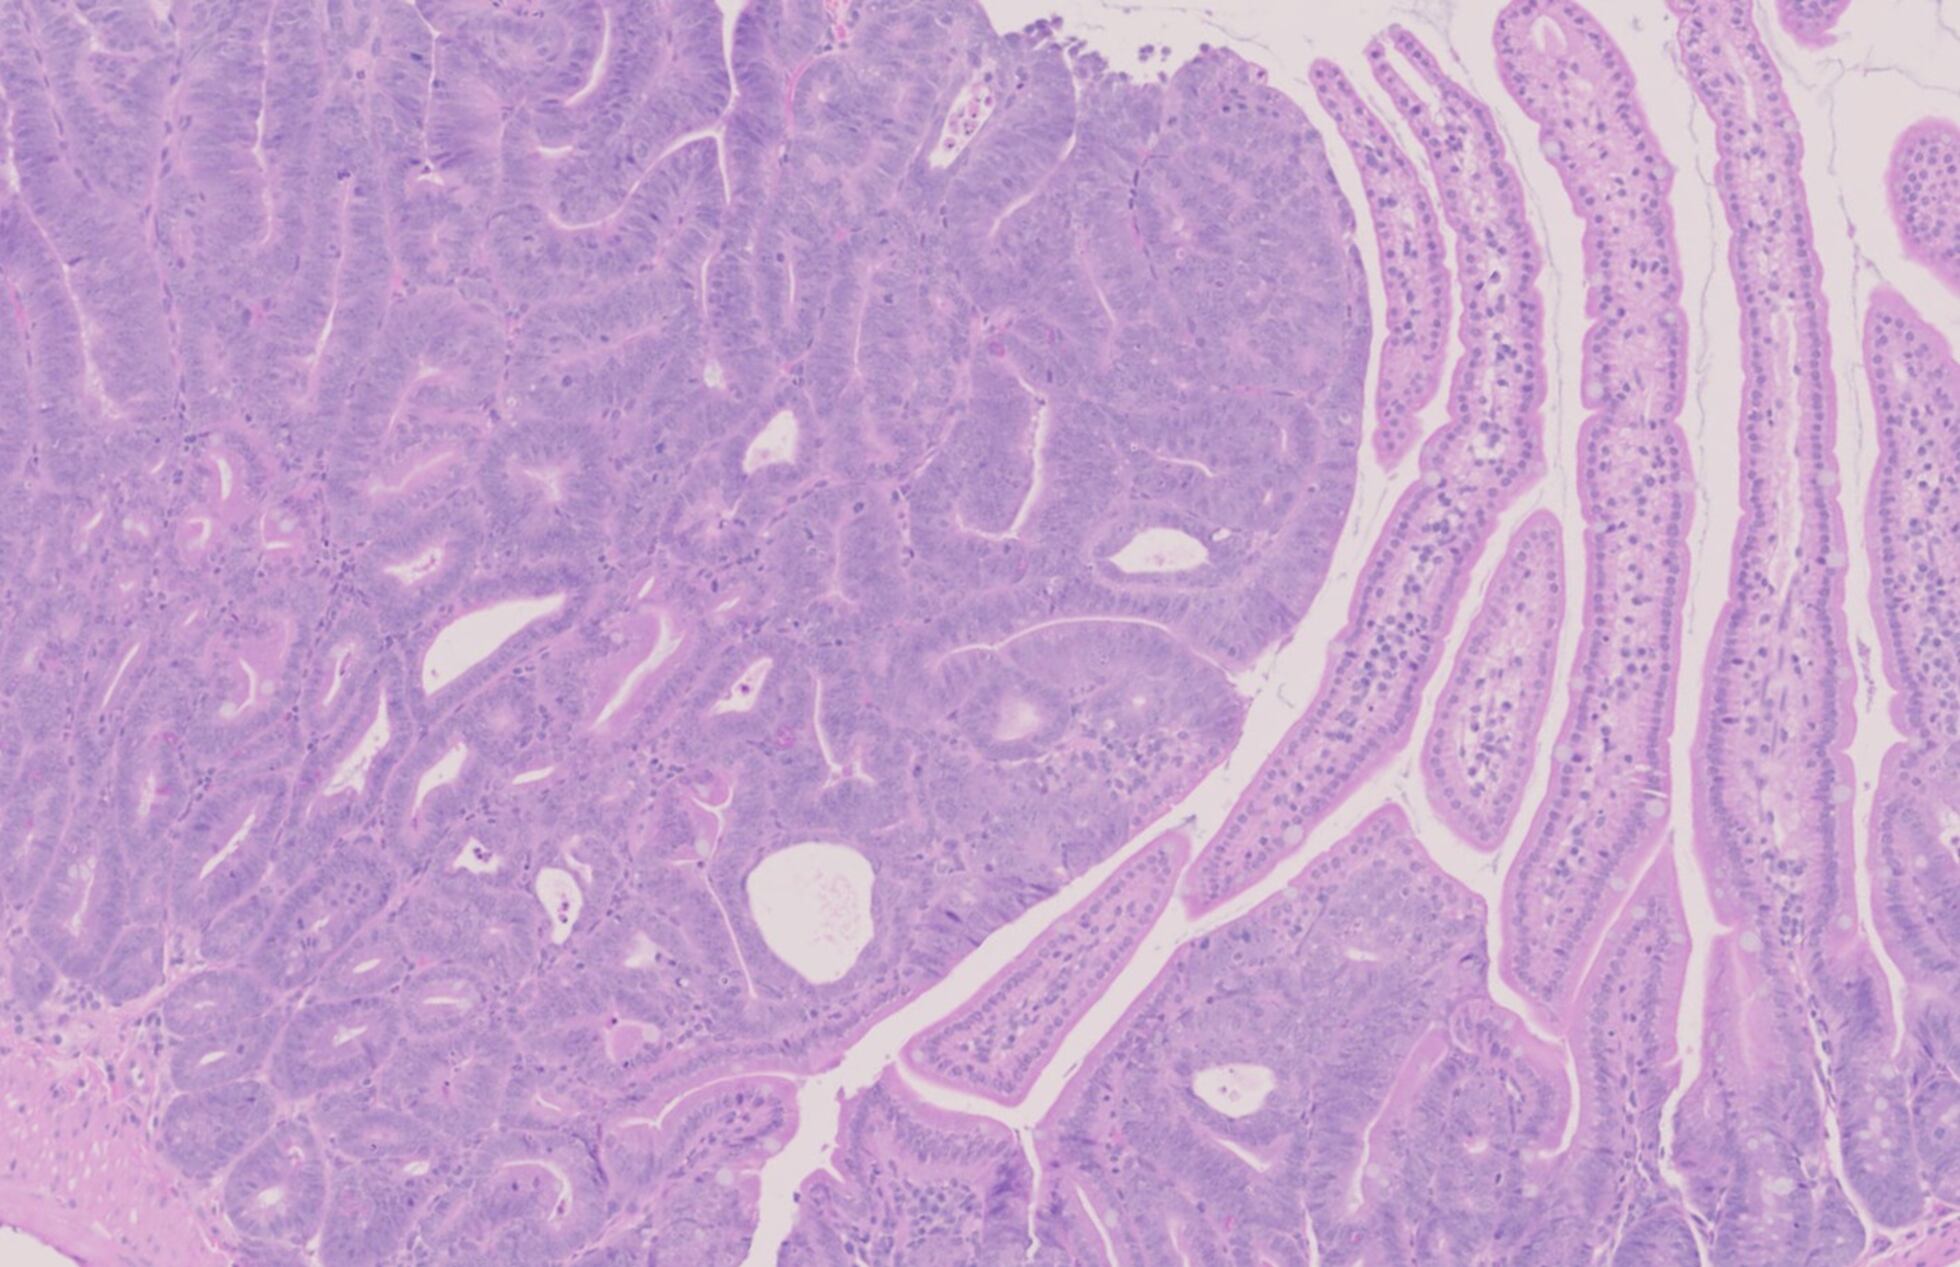

Şimdi ise Sciencedergisinde yayımlanan kapsamlı bir çalışma, yüzlerce tümör örneğini analiz ederek evcil kedinin en kapsamlı onkogenomunu ortaya koydu.

493 kediye ait tümör ve sağlıklı doku örneklerini inceleyen ekip, “kedilerde kanseri yönlendiren genleri tanımlamak ve onların onkogenomunu ortaya çıkarmak” amacıyla yola çıktı.

Bu genler, insan kanserinde rol oynayan yaklaşık 1.000 genle benzer yapı ve işleve sahip. Araştırmacılar; osteosarkomdan pankreas adenokarsinomuna, meme kanserlerinden diğer tümör türlerine kadar 13 ana tümör tipinden örnek topladılar.

Örneğin meme kanseri: Çalışma, agresif meme kanseri türlerine yol açan yedi geni belirledi. Bunlar arasında en yaygın olanı FBXW7 geni.

Kedilerdeki tümörlerin yarısından fazlasında bu gende mutasyon bulunuyor. Özellikle “üçlü negatif meme kanseri” (triple-negative breast cancer) olarak bilinen agresif alt tür, genç kadınlarda görülen bir hastalık olarak biliniyor.

Kedilerde ise bu tür çok daha sık görülüyor ve oldukça agresif seyrediyor.